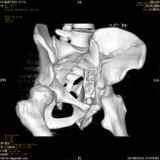

Уважаемые коллеги! Хотелось бы услышать совет по тактике лечения представлленого больного.Поступил после лечения в одном изотделений области. Травма 2,5 месяца назад. После выведенияиз шока был произведен остеосинтез перелома бедра, предплечья, до перевода к нам проводилосьвытяжение по оси шейки бедра за стержень, введенный в большой вертел. На сегодня деформацияригидна, клинически мобильности не определяется. Заранее признателен. P.S. Данный вид травм не включен в перечень "высокотехнологичных операций", направить длялечения по квотам Минздрава очень сложно.

Все-таки надо бы начать не с КТ, а с обзорного снимка таза и косых проекций впадины.

Это обзорные и косые снимки

Привет, Леонид. Оскольчатый высокий двухколонный перелом в такие сроки трогать не надо, т.к. это про такие переломы сказано: "кто с ножом на Ж. пойдет тот в ней и останется...".